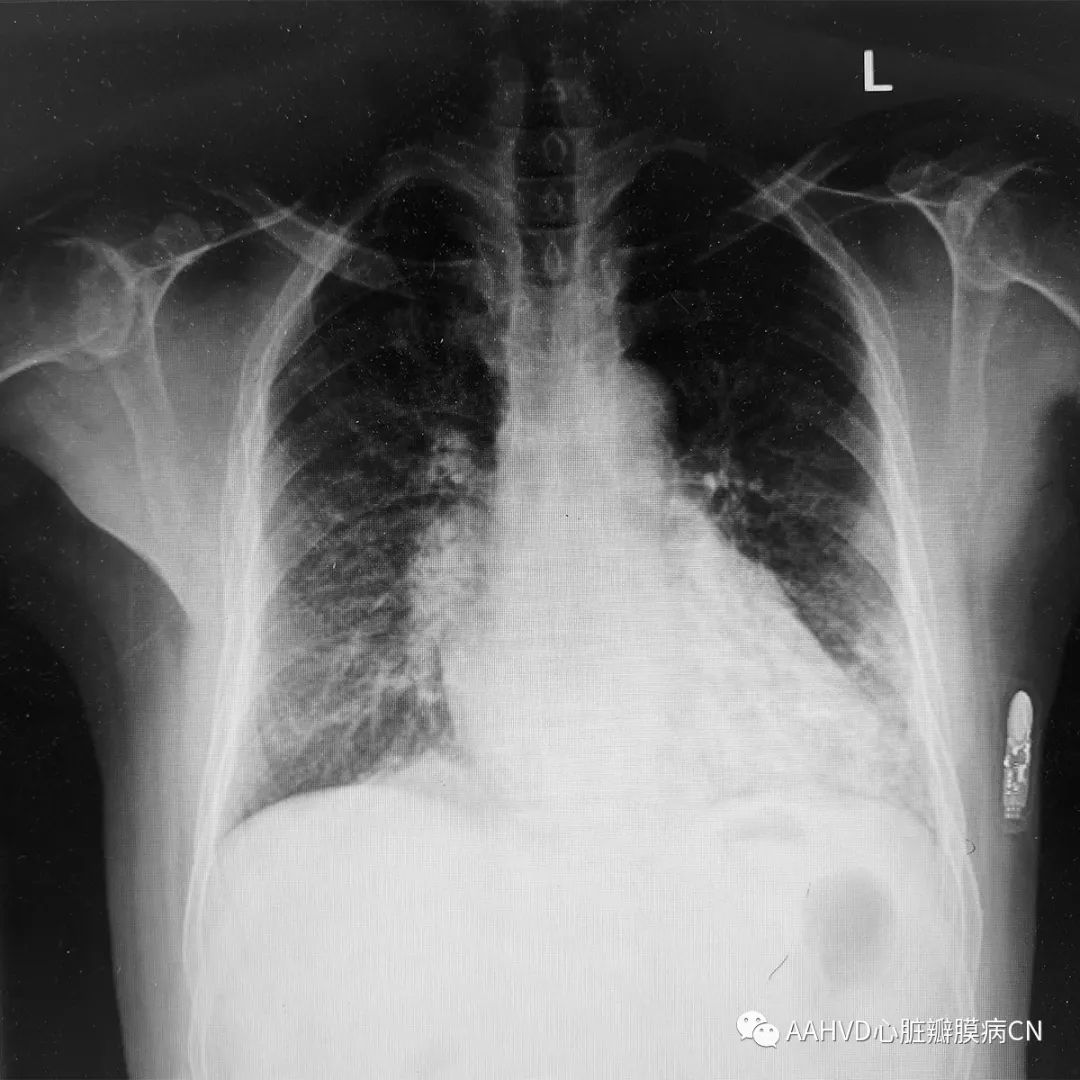

术前胸片

640_2

术前经胸超声:

风湿性心脏病,二尖瓣返流面积11.1cm²(重度返流),瓣口面积1.7cm²(轻度狭窄),前向流速101cm/s,主动脉瓣轻度狭窄并关闭不全。